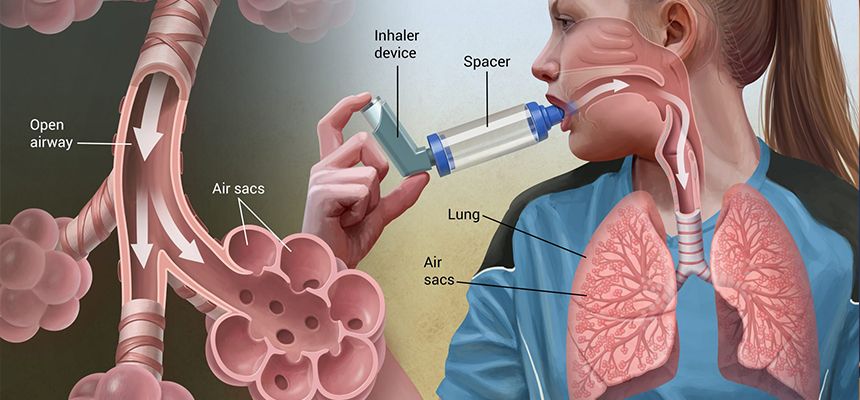

पेडियाट्रिक पल्मोनोलोजी एण्ड इन्टेन्सिभ केयरमा डीएम गर्ने पहिलो सरकारी डाक्टर